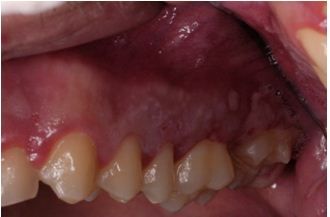

The image here shows primary herpes simplex virus type 1 (HSV-1) infection localized to the attached gingival tissue. HSV-1 infection of the oral mucosa is typically short-lived and not a major medical concern, except in cases involving immunocompromised patients and/or central dissemination.

Photo courtesy of Dr Federico Brugnami